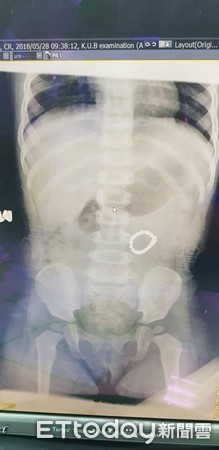

▲女童誤吞巴克球,巴克球在腸道內吸附成圓環狀。(圖/童綜合醫院提供)

超強磁力巴克球惹禍!日前一名1歲紀姓女童因肚子痛又出現疑似腸病毒的症狀,到醫院就診後確認罹患腸病毒,沒想到進行X光與腹部超音波檢查時,赫然發現腹部出現疑似手鍊形狀的影像。童綜合醫院小兒外科主任郭敏勇進行小腸部分切除取出異物,才發現女童的小腸中有18顆的巴克球。

郭敏勇表示,女童應該是分顆吞食巴克球,巴克球才會在腸道內吸附成一個圓環,若是同時吞食則可能吸附成一團後由消化系統排出,且這則案例非常特殊,巴克球進入小腸後,在空腸腸段吸附成一圈圓環。

▲女童的X光照片中,可以看見腸內有手鍊狀異物。(圖/童綜合醫院提供)